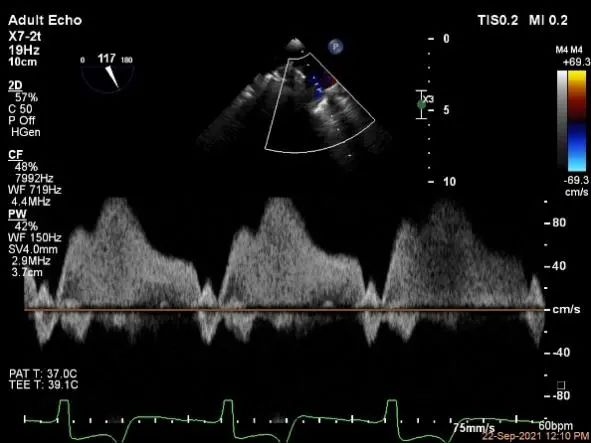

麻醉状态下肺静脉血流频谱

MVA:7.8cm²,平均跨瓣压差:1mmHg

评估二尖瓣瓣口平均跨瓣压差:1mmHg

肺静脉血流频谱恢复正常